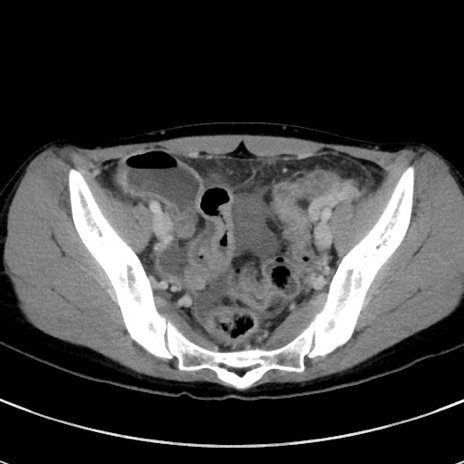

症例17(横断像)

【症例】20歳代女性

【主訴】嘔吐、下腹部痛

【現病歴】昨日夕食後に嘔吐し下腹部痛が出現。本日になっても嘔吐持続し改善しないため来院。

【身体所見】意識清明、BT 37.2℃、BP 108/67mmHg、腹部:平坦、やや硬、下腹部正中から右にかけて圧痛あり、反跳痛軽度あり、tapping pain(+)。

【データ】WBC 13600、CRP 14.94